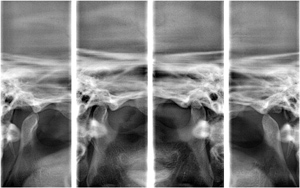

1﹒專為牙醫設計的專業牙科影像軟體,結合所有牙科影像並提

......供各種影像的運用。

2﹒可快速將拍攝畫面導入影像軟體中,提供多項影像的操作功

......能例如:植牙、矯正.....等。